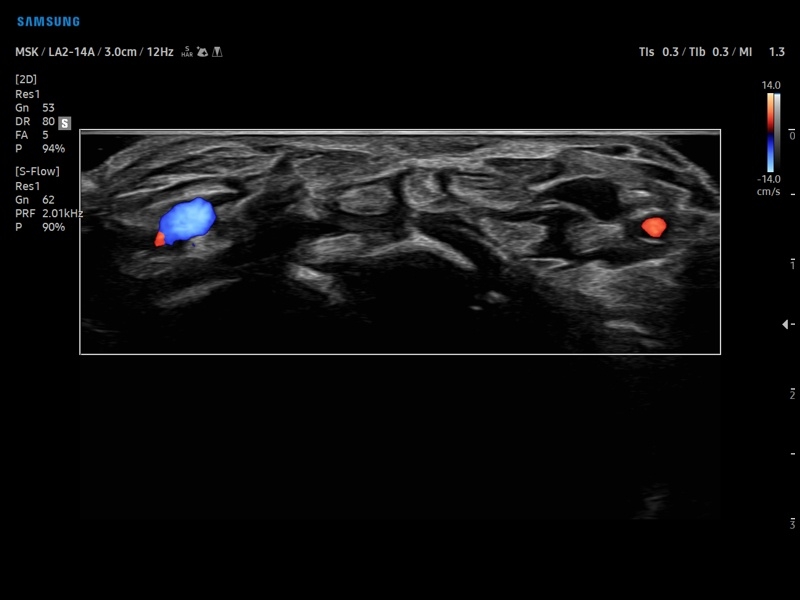

• Модуль NerveTrack – автоматическое определение срединного нерва в поперечном сечении с использованием искуственного интеллекта.